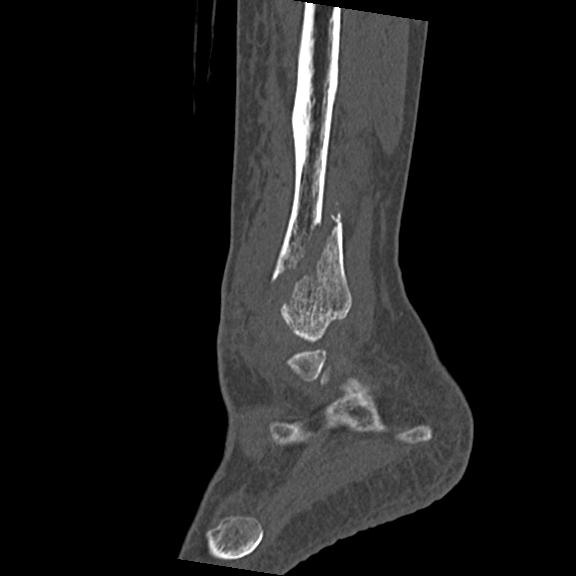

102755 1/4 2R 1/15 2R 右足関節 68歳女性 右三果脱臼骨折